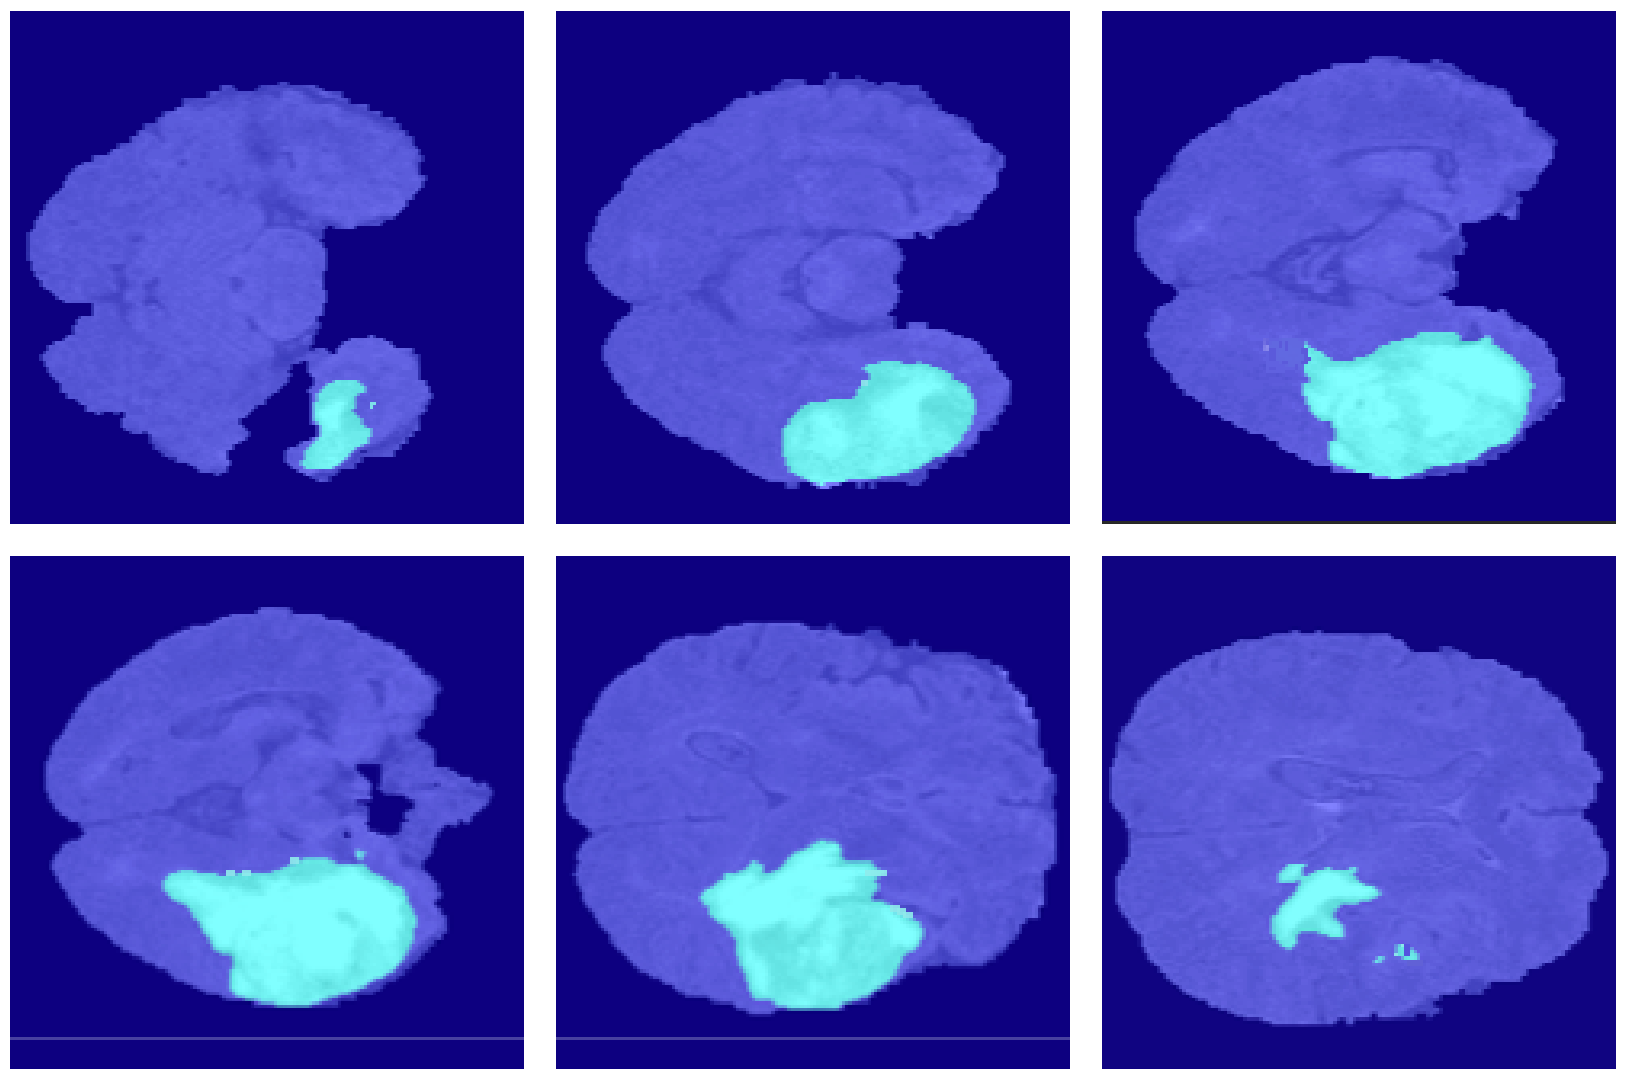

4.2. Segmentation Results

5. Discussion